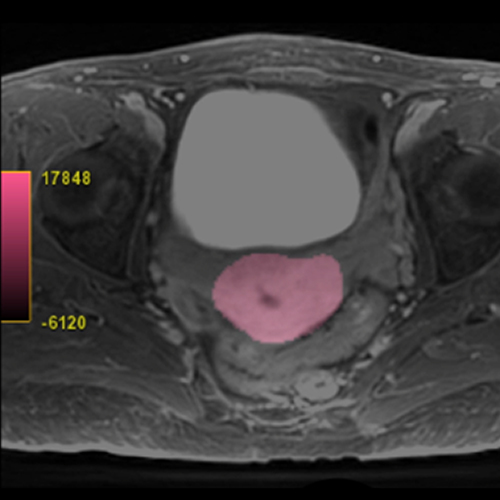

Our Uterine Fibroid Service offers an advanced 3D imaging solution designed to support the assessment and treatment planning for uterine fibroids. By accurately calculating the volume of the uterus and providing detailed mapping of the pelvic vasculature, this service may assist in the management of fibroids. Precise measurements of the uterus' volume are important in gauging the extent of fibroids present, which is essential for understanding the severity of the condition and planning appropriate interventions.

Additionally, this imaging may be useful for effective planning of uterine fibroid embolization (UFE), a minimally invasive procedure that aims to shrink fibroids by blocking their blood supply. This approach ensures that treatment is precisely targeted, maximizing efficiency and outcomes. UFE involves using imaging guidance to deliver small particles that obstruct the blood flow to fibroids, leading to their reduction.

Our service also provides follow-up measurements to monitor the response to various therapies, such as High-Intensity Focused Ultrasound (HIFU), UFE, or myomectomy, allowing for the adjustment of treatment plans based on the progress observed. With nearly 90 percent of women experiencing symptom relief from fibroids through such treatments, our Uterine Fibroid Service is committed to delivering targeted and effective solutions for fibroid management, enhancing patient care and outcomes.